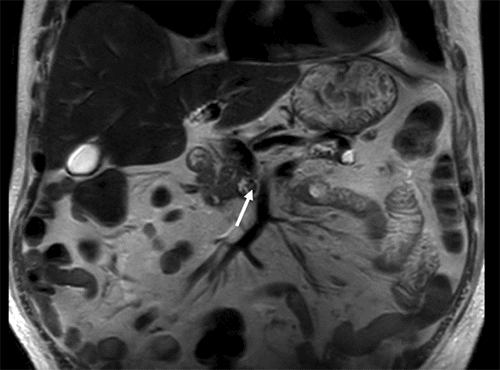

Magnetic resonance imaging (MRI) of the right lower extremity showed findings consistent with noninfectious osteomyelitis—diffuse soft tissue edema around the right ankle with effusion, fluid in the posterior tibialis tendon sheath with synovial and muscle enhancement, and osseous hyperenhancement of the mid-tibial shaft with periosteal edema (Figure 2). Computerized tomography (CT) scan of the abdomen and pelvis with IV contrast was notable for soft tissue stranding around the pancreatic head, a large pancreatolith in the body of the pancreas, and a non-occlusive superior mesenteric vein (SMV) thrombus (Figure 3). MRI of the abdomen demonstrated pancreatic ductal dilation and a focal area of pancreatic necrosis in the uncinate directly adjacent to the SMV (Figure 4).

Figure 4. Coronal T2W MRI Showing Necrosis of Uncinate Process (arrow) Directly Adjacent to SMV. Published with Permission